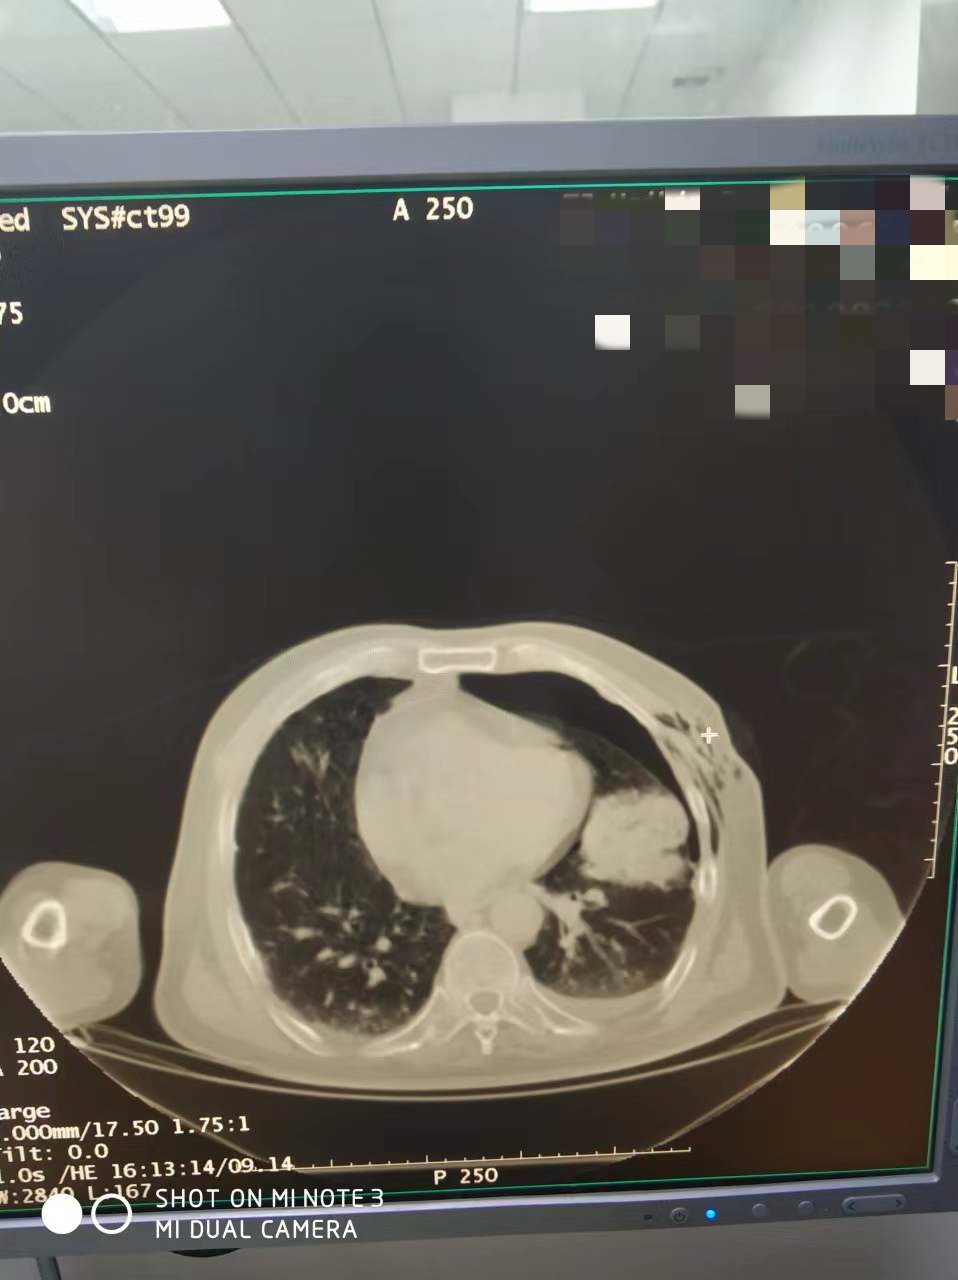

上一篇:2022年4月份肺部氩氦刀手术